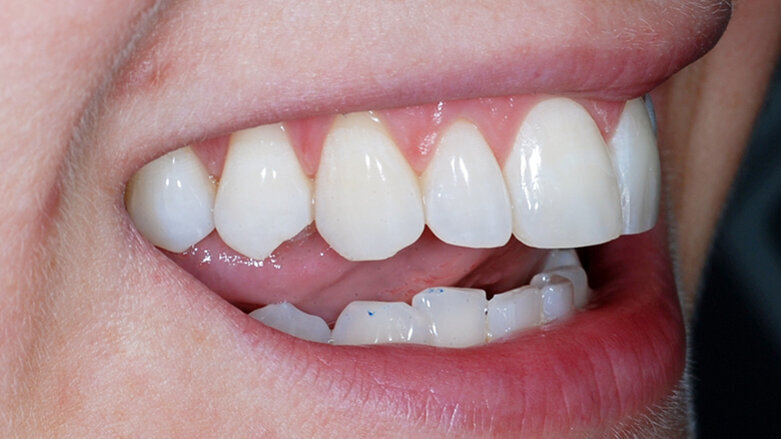

Fig. 15: Post treatment anterior

Fig. 16: Post treatment right lateral

Fig. 17: Post treatment left lateral

Fig. 18: Post treatment right lateral open bite

Fig. 19: Post treatment retracted

The patient was very satisfied with the results, especially the fact I was able to improve her smile without affecting the integrity of the enamel. I sent before and after images to the patient at the end of her treatment pathway so that she could see the difference, and she was amazed at how much the aesthetics of her teeth had changed. I was also very happy with the outcome – with the help of the IAS Academy and digital planning tools, treatment was safe and predictable.